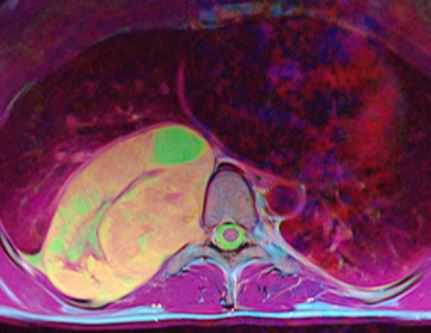

МРТ позвоночника. Аксиальная Т2-взвешенная МРТ грудного отдела. Невринома по типу “песочных часов”. Цветовая обработка изображения.

При МРТ позвоночника могут быть выявлены не только дегенеративные заболевания и грыжи дисков, но и опухоли. Экстрадуральные опухоли, в основном метастазы в позвонки, рассматриваются нами в специальной статье. Интрадуральные опухоли могут быть экстрамедуллярными (внутри позвоночного канала, но вне спинного мозга) и интрамедуллярными (собственно спинного мозга). И те и другие могут проявляться миелопатическим синдромом. МРТ в СПб спинного мозга осуществляется одновременно с МРТ позвоночника по стандартным программам, с добавлением МРТ с контрастированием. Стойкое подозрение на опухоль мозга позволяет исследовать область прицельно. На открытом МРТ срезы чуть толще, однако, обычно это не сказывается на качестве диагностики. МРТ СПб позволяет выбирать место выполнения МРТ, мы рекомендуем Вам обследоваться у нас, так как имеем большой опыт МРТ позвоночника в нейрохирургии.

Невриномы (шванномы) и нейрофибромы составляют примерно половину опухолей этой локализации и 35% от всех спинальных опухолей. Гистологически невриномы происходят из шванновских клеток оболочек нерва (леммоцитов), прилегающих к заднему корешку. Обычно диагностируются они в возрасте 20 - 50 лет, у мужчин проявляются несколько в более молодом возрасте, чем у женщин. Они почти всегда одиночные, инкапсулированные, располагаются в любом отделе, но чуть чаще в поясничном или верхнем шейном. Множественные невриномы встречаются исключительно редко при нейрофиброматозе типа II. Нейрофибромы состоят из шванновских клеток и фибробластов, некоторые окружают задний корешок. Они почти всегда множественные и связаны с нейрофиброматозом типа I (болезнь Реклингхаузена). От 2 до 12% нейрофибром перерождаются злокачественно, превращаясь в нейрофибросаркомы. Несмотря на различие в гистологии характер роста опухолей одинаковый. Около 15% из них распространяются в экстрадуральное пространство через одно или несколько межпозвоночных отверстий, приобретая вид “песочных часов”. Такой тип роста особенно типичен для шейной локализации. На рентгенограммах рост по типу «песочных часов» может быть выявлен по расширению межпозвоночного ответстия и эрозии корня дуги. Клинические проявления неврином и нейрофибром состоят в радикулопатическом и миелопатическом синдромах.

На МРТ Т1-взвешенного типа и невриномы, и нейрофибромы изо- или слегка гипоинтенсивны по отношению к спинному мозгу. Однако, встречаются случаи и повышенного сигнала за счет сокращения Т1 мукополисахаридами, связанными с водой. Протонная плотность при МРТ повышена, а на Т2-взвешенных МРТ они чаще неоднородные, могут быть очень яркие участки, где имеется высокое содержание воды, и сравнительно низкого сигнала, особенно в центре. Обе опухоли хорошо контрастируются при МРТ. По форме невриномы округлые, границы ровные, четкие. Нейрофибромы вытянуты вдоль корешка, что лучше видно на корональных МРТ. Размеры могут быть самыми различными.